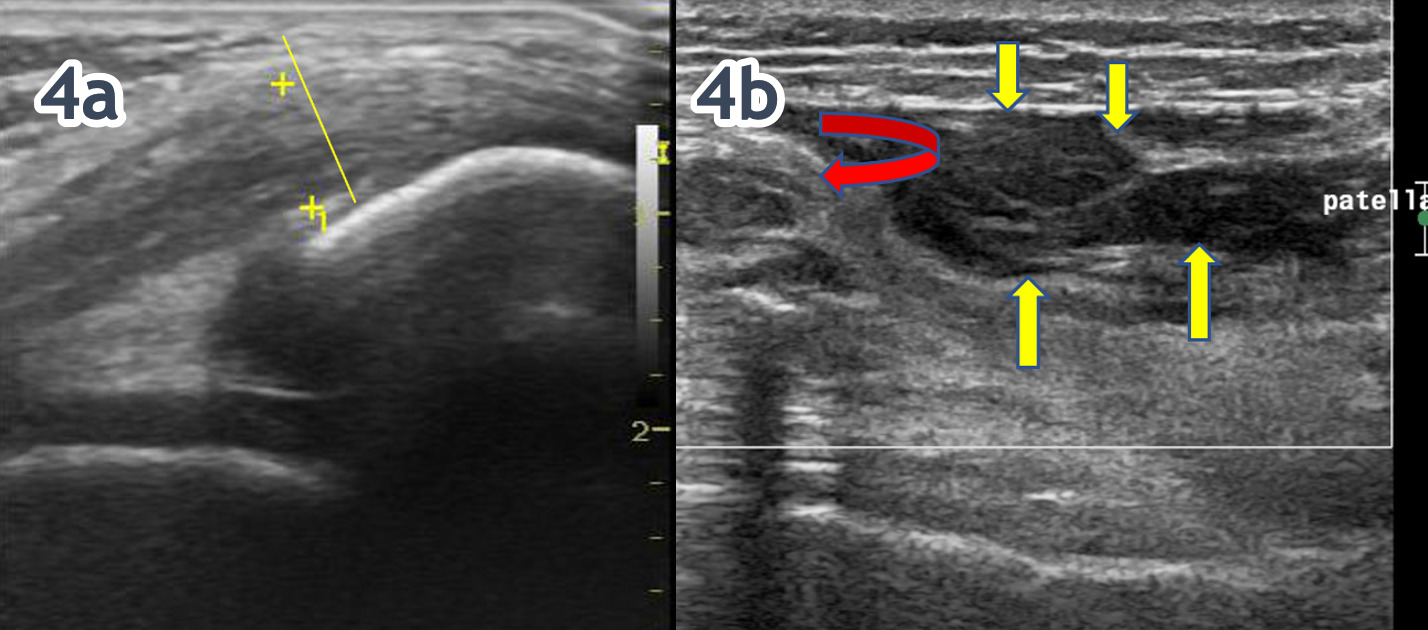

Traditionally, quadricep complex soft tissue injury has been difficult to quantify with the clinical evaluation. Clinical success is always predicated upon an accurate diagnosis and understanding of the pathological process. MSK-US imaging of the has revolutionized the diagnosis of quadriceps muscle and tendon injuries. It provides high-resolution images and animations that enable successful visualization and separation of soft tissues from adjoining bones and ligaments. While a careful history and a thorough physical examination are important steps in the assessment of quadriceps pathology, MSK-US provides high-resolution static of dynamic images that enable successful visualization and separation of soft tissues from adjoining bones and ligaments. MSK-US has become an invaluable component in diagnosing quadriceps muscle and tendon injuries due to its ability to clearly display the affected structures without exposing the patient to radiation or utilizing ionized contrast media. MSK-US can provide precise visualization of edema and can easily distinguish between benign and potentially pathological findings which make it an integral part of any holistic evaluation of quadriceps muscle tendon injury. The speed and accuracy of ultrasound imaging make it a useful tool in differentiating muscle contusion from tendinopathy or strain. In addition to the diagnostic benefits, MSK-US is also beneficial for monitoring progression and recovery of quadriceps muscle and tendon injuries. The accuracy of images helps clinicians evaluate patient progress during physical therapy sessions and make necessary adjustments to treatment plans if needed. This allows for more precise tracking of muscle healing, enabling clinicians to identify any setbacks early on and provide timely intervention if required.

In conclusion, MSK-US is an effective diagnostic tool for assessing quadriceps muscle and tendon injuries. MSK-US has minimal risk with no radiation involved and it can provide valuable information about the extent and progression of injury. By understanding MSK-US and its benefits, medical professionals can better diagnose and treat patients with quadriceps muscle and tendon injuries, leading to more successful outcomes. This makes it an invaluable tool for healthcare professionals when treating musculoskeletal disorders. MSK-US should always be used alongside other techniques such as physical examinations, laboratory tests and patient history in order to accurately diagnose quadriceps muscle and tendon injuries. MSK-US is essential for providing insight into the structures affected by injury and helps clinicians create tailored physical therapy plans that lead to optimal outcomes. With its accuracy, precision, and non-invasive nature, MSK-US has become an integral part of diagnosing and treating quadriceps muscle injuries. The goal of this article is to provide a few tips and tricks to assist in using MSK-US as a diagnostic tool for the assessment of quadriceps pathology.